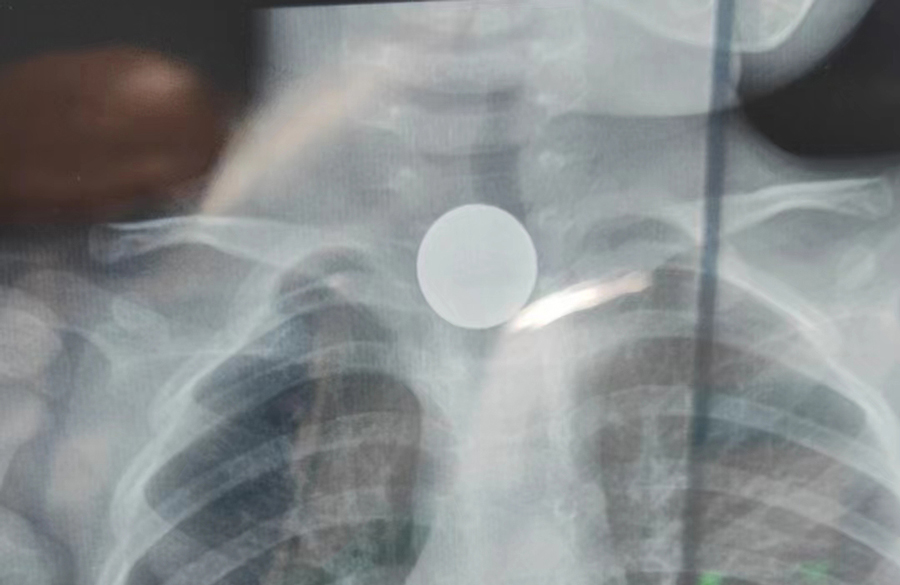

了解了患儿的情况后,国家儿童医学中心、首都医科大学附属北京儿童医院耳鼻喉头颈外科常驻专家、啪啪网 副院长张薇仔细看了患儿的X光片,明确了异物的存在和准确位置。由于异物存留时间长,食道是否有肉芽增生、有无穿孔等情况都不明确,张薇副院长决定采用全麻下通过食道镜直视下行异物取除术。

手术非常顺利,当卡在小强食道入口下方的硬币被取出后,家长才知道,原来导致孩子受罪一个多月的竟是一枚硬币。由于硬币卡在食道内时间太长,被取出时颜色已经发黑。术后,小强不能像其他孩子一样迅速恢复呼吸,而是住进了ICU。原来是由于异物坎顿,食道入口关闭不全,小强进食时总会呛咳,导致反复吸入性肺炎,肺功能明显受损,肺内通气量不足、反复发热,全身身体机能下降,所以不能及时苏醒。不过,经过医务人员进一步治疗后,小强现已康复出院。